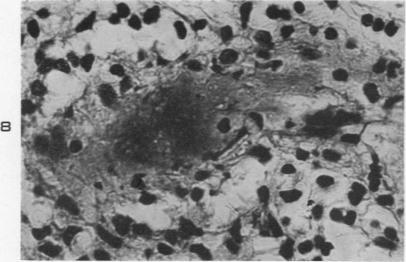

Asymptomatic focal arteritis of the appendix; 88 cases.

Am J Pathol. 1951 Mar-Apr;27(2):247-63.